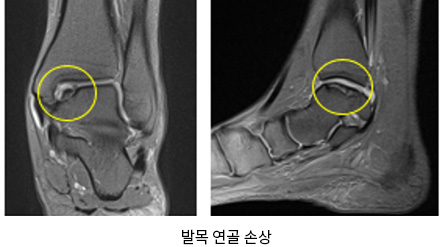

발목인대/연골손상

발목을 심하게 접지르거나 운동 시 반복적인 자극이 가해지는 경우 발목 인대의 손상이 발생하게 됩니다. 발목뼈를 덮고 있는 연골이 여러 원인에 의해 손상되며, 치료 없이 방치되는 경우 퇴행성 관절염으로 진행됩니다.